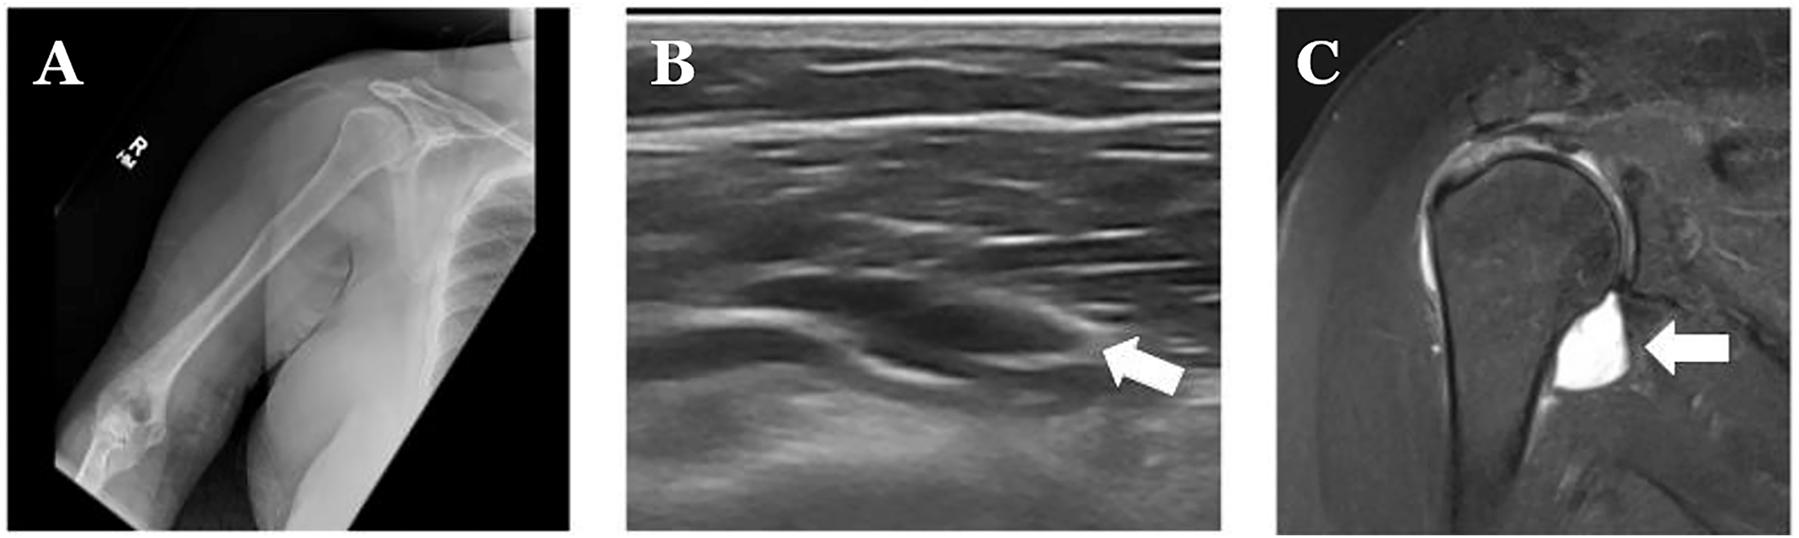

Radiographic evaluation of the right shoulder. (A) Normal X-ray without bony or soft-tissue abnormalities. (B) Abnormal point-of-care ultrasound (POCUS) evaluation of the right shoulder, with the arrow demonstrating tendon deficit. (C) Fluid MRI results, with the arrow showing rupture of the supraspinatus tendon with 1.8 cm stump retraction.

In May 2021, a 53-year-old woman reported falling off her sofa and injuring her right shoulder 4 h before arrival in the emergency department (ED). Since her injury, she has been unable to utilize or raise her right arm. Physical examination demonstrated that the patient was holding her shoulder in an internally rotated position, with limited active and passive range of motion of the shoulder due to pain. The patient was unable to participate in shoulder maneuvers, such as the Empty Can Test, due to pain. The rest of the neurovascular examination of her upper extremity was within the normal limits. An X-ray and bedside ultrasound utilizing a linear probe was performed. For the sonographic image, the patient was sitting upright with her elbow extended and her shoulder internally rotated. The linear probe was placed inferior to the acromion with the marker faced to the anterior and then again to the cephalad. Findings are found in Figure 1. The patient was subsequently diagnosed with a supraspinatus tendon rupture and sent for outpatient MRI and orthopedic follow-up. Because her orthopedic surgeon’s outpatient and procedure notes are unable to be seen from the ED’s electronic medical record, there is no information on her follow-up.

Rotator cuff injuries can be difficult to definitely diagnose within the ED without MRI capabilities. Point-of-care ultrasound (POCUS) is a valuable tool to accurately determine the presence of full-tendon ruptures, with high sensitivity and specificity of over 90 % [1, 2]. Hypo-echoic fluid disrupting the tendon, which was seen in two different ultrasound orientations, suggests full-thickness tears [3]. These hypo-echoic defects need to disrupt the hyper-echoic tendon fibers through the entire muscle [4]. The patient was placed in an arm sling, and the outpatient MRI occurred 6 days later, which confirmed the diagnosis. If the physical examination suggests a tendon tear, a diagnostic ultrasound should be performed because patients with positive findings can be prioritized for further characterization by MRIs prior to appropriate surgical consultations [3].